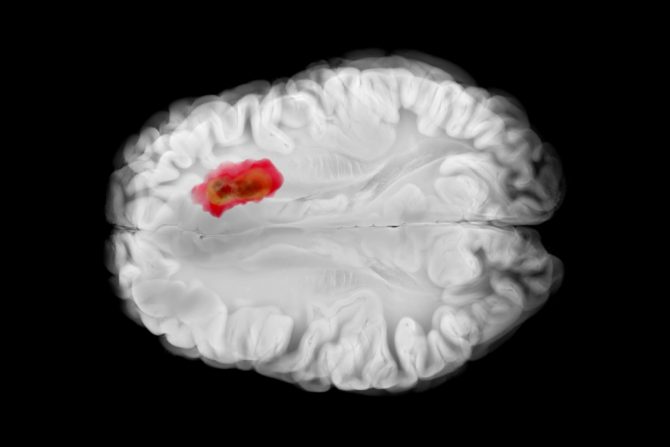

Naučnici sa University of Florida razvili su mRNA vakcinu koja pokreće žestok imuni odgovor u borbi protiv glioblastoma, najagresivnije malignog tumora mozga. Nova mRNA vakcina razvijena po sličnoj tehnologiji kao mRNA covid 19 vakcine brzo je reprogramirala imuni sistem da napadne najagresivniji tip tumora mozga u prvom kliničkom ispitivanju na ljudima. Ovo otkriće, objavljeno u Cell, predstavlja potencijalni novi način da se regrutuje imuni sistem za borbu protiv ozloglašenog raka otpornog na lečenje.

U prvom kliničkom ispitivanju na ljudima na četiri odrasla pacijenta, vakcina protiv raka mRNA razvijena na University of Florida brzo je reprogramirala imuni sistem da napadne glioblastom, najagresivniji i smrtonosniji tumor mozga. Rezultati su dobijeni na osnovu ispitivanja na psima - 10 kućnih ljubimaca koji pate od tumora mozga koji se prirodno pojavljuju, a čiji su vlasnici odobrili njihovo učešće u studiji, jer nisu imali druge opcije lečenja, kao i na osnovu dokaza iz pretkliničkih ispitivanja laboratorijskih miševa. Kako je najavljeno, ovo otkriće će sada biti testirano u prvoj fazi pedijatrijskog kliničkog ispitivanja raka mozga.

Prema poslednjim infromacijama, revolucionarna mRNA vakcina protiv raka uspela je da izbriše smrtonosne tumore mozga u ranim ispitivanjima na ljudima bez hemoterapije ili zračenja. Testirano na četiri pacijenta sa glioblastomom, vakcina je reprogramirala njihov imuni sistem u roku od 48 sati da napadne tumor. Napravljena od tumorskih ćelija svakog pacijenta i isporučen preko lipidnih nanočestica, pokazala je uspeh sličan ranijim testovima na miševima i psima i sada se kreće u Fazu 1 pedijatrijskih ispitivanja.